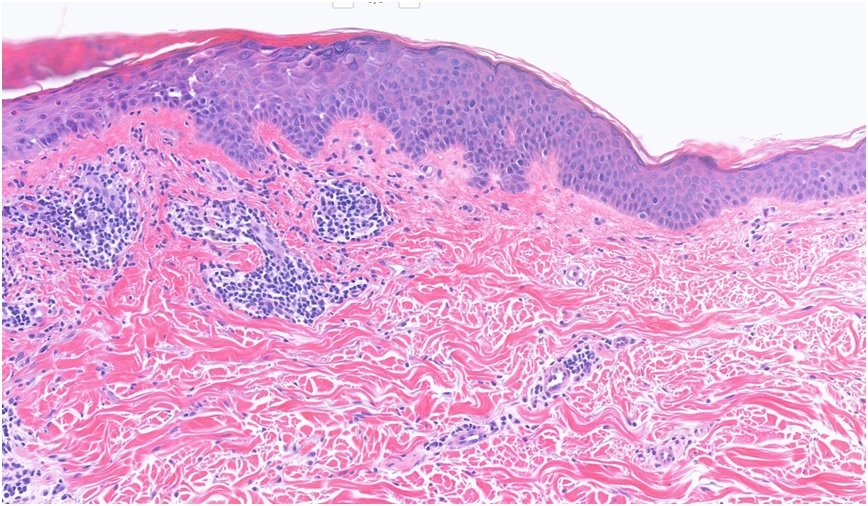

59F, Abdomen Biopsy Rash on torso; did respond to Elocon but recurred once treatment cease. Very small red/pink papules ?Guttate psoriasis